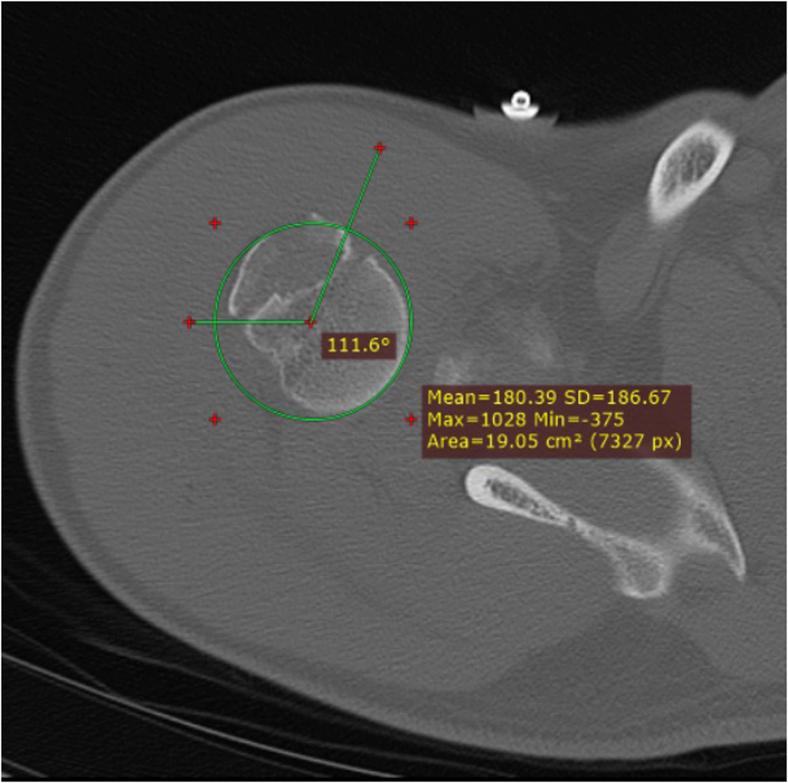

Computed tomography scans of 19 patients with HSL and 18 patients with GTF after first-time shoulder dislocations were analyzed. We assessed the location by measuring height in relation to the highest point of the humerus and angles for the origin (most medial point of lesion), center, and endpoint (most lateral point of lesion) between GTF and HSL and the bicipital groove. For both GTF and HSL, we assessed whether infraspinatus and supraspinatus insertions were involved and whether they were off-track or on-track.

Measured from the bicipital groove, HSLs and GTFs have different origins (153˚ vs. 110˚;  < .0001, respectively), centers (125˚ vs. 60˚;  < .0001, respectively), and endpoints (92˚ vs. 37˚;  < .0001, respectively). HSLs had a higher position (0.76 cm vs. 1.71 cm;  < .0001), involved the supraspinatus footprint less often (16% vs. 72%;  = .0008), and were less likely to be off-track (31% vs. 94%;  = .0002). Half of the GTF were on the lateral side of the glenoid track and thus extra-capsular, versus 0% of HSL.